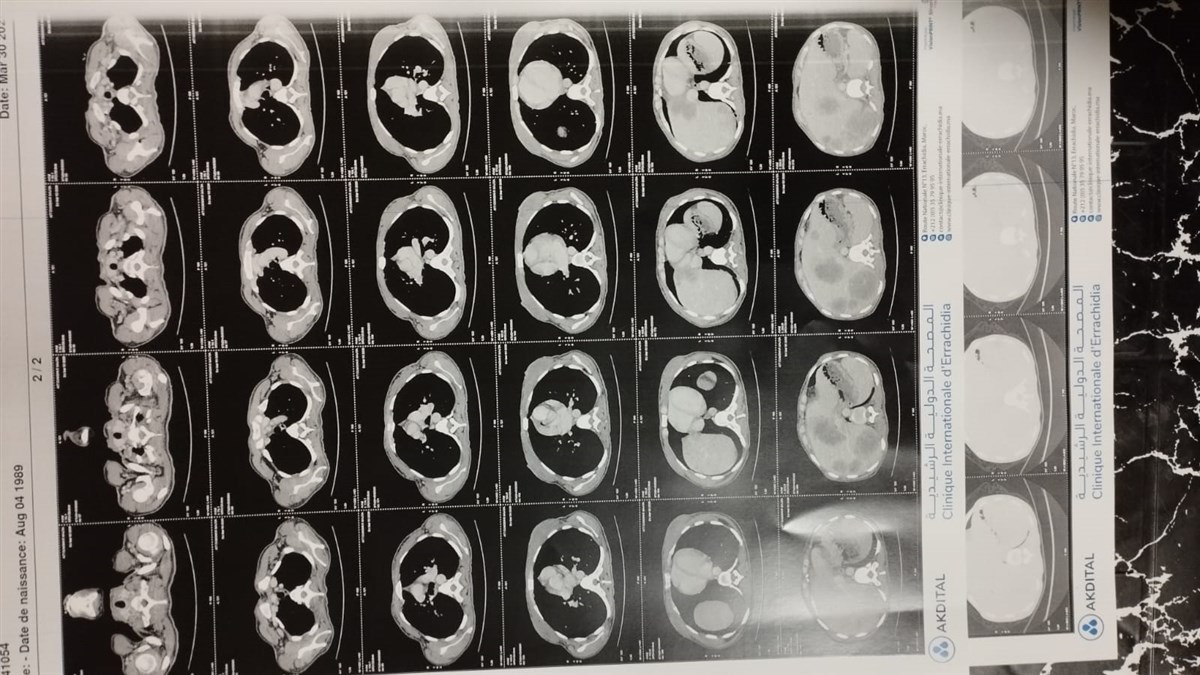

Majda is moeder van een lief meisje van 15 maanden. Ze woont in het zuiden van Marokko, waar het leven al zwaar genoeg is. Nu heeft Majda te horen gekregen dat ze kanker heeft, en niet zomaar één vorm: de ziekte is uitgezaaid. De behandelingen die ze nodig heeft, zijn intensief en kostbaar.

Zonder de juiste chemokuren en pijnmedicatie heeft Majda geen kans op genezing. Maar de kosten zijn hoog en de middelen ontbreken. Elke dag telt, elke behandeling is een stap dichter bij hoop. Voor Majda, maar vooral voor haar kleine dochtertje die haar moeder zo hard nodig heeft.